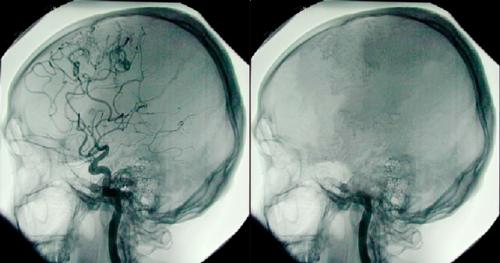

Хотя многие люди прошли через подобный опыт, наука оказалась не в состоянии дать объяснения феномену клинической смерти.

Отдельные ученые предполагают, что опыт нахождения на грани смерти можно объяснить лишь результатом галлюцинаций при повреждения мозга.